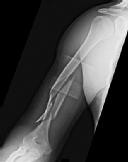

Figures 1 and 2 are the radiographs of a 19-year-old man with a closed right humeral shaft fracture as well as a right femoral shaft fracture and a left ankle fracture-dislocation after a motor vehicle collision. On initial examination, he is noted to have a complete radial nerve palsy of his right upper extremity.

Postoperative radiographs are shown in Figures 3 and